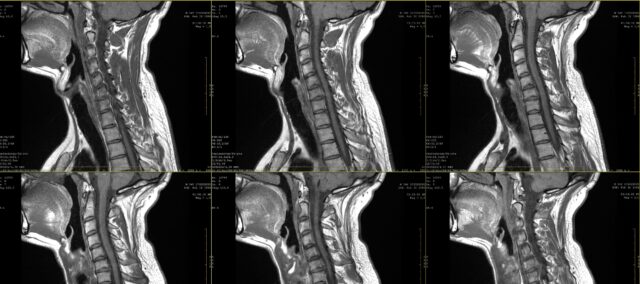

Để tìm hiểu sự phù hợp giữa các bản vẽ đau rễ thần kinh và các phát hiện MRI, nghiên cứu này bao gồm những người tham gia có tiền sử đau dai dẳng trong 2 tháng, được chẩn đoán mắc bệnh lý rễ thần kinh cổ trên MRI. Chẩn đoán này được đưa ra bởi một bác sĩ phẫu thuật thần kinh dựa trên thông tin lâm sàng và các phát hiện MRI được đánh giá bởi một bác sĩ X quang.

Các hình vẽ về cơn đau được thực hiện trên biểu đồ cơ thể, cả góc nhìn từ trước ra sau. Sau đó, các biểu đồ này được trình bày cho 4 bác sĩ lâm sàng (2 bác sĩ phẫu thuật và 2 chuyên gia vật lý trị liệu) - những người không biết về rễ thần kinh bị ảnh hưởng như được xác định trên hình ảnh chụp MRI. Họ chỉ nhận được thông tin rằng tất cả bệnh nhân được trình bày bản vẽ về cơn đau đều được chẩn đoán mắc bệnh lý rễ thần kinh cổ ở một mức độ duy nhất giữa C4 và C7. Dựa trên bản vẽ cơn đau của bệnh nhân, họ phải xác định mức độ cột sống bị ảnh hưởng. Sự phù hợp giữa mức độ cột sống được xác minh bằng MRI và phán đoán dựa trên bản vẽ cơn đau của bác sĩ lâm sàng được đánh giá bằng kappa. Hơn nữa, sự thống nhất giữa các giám định viên cũng được xem xét bằng thống kê kappa. Giá trị Kappa được diễn giải như sau: